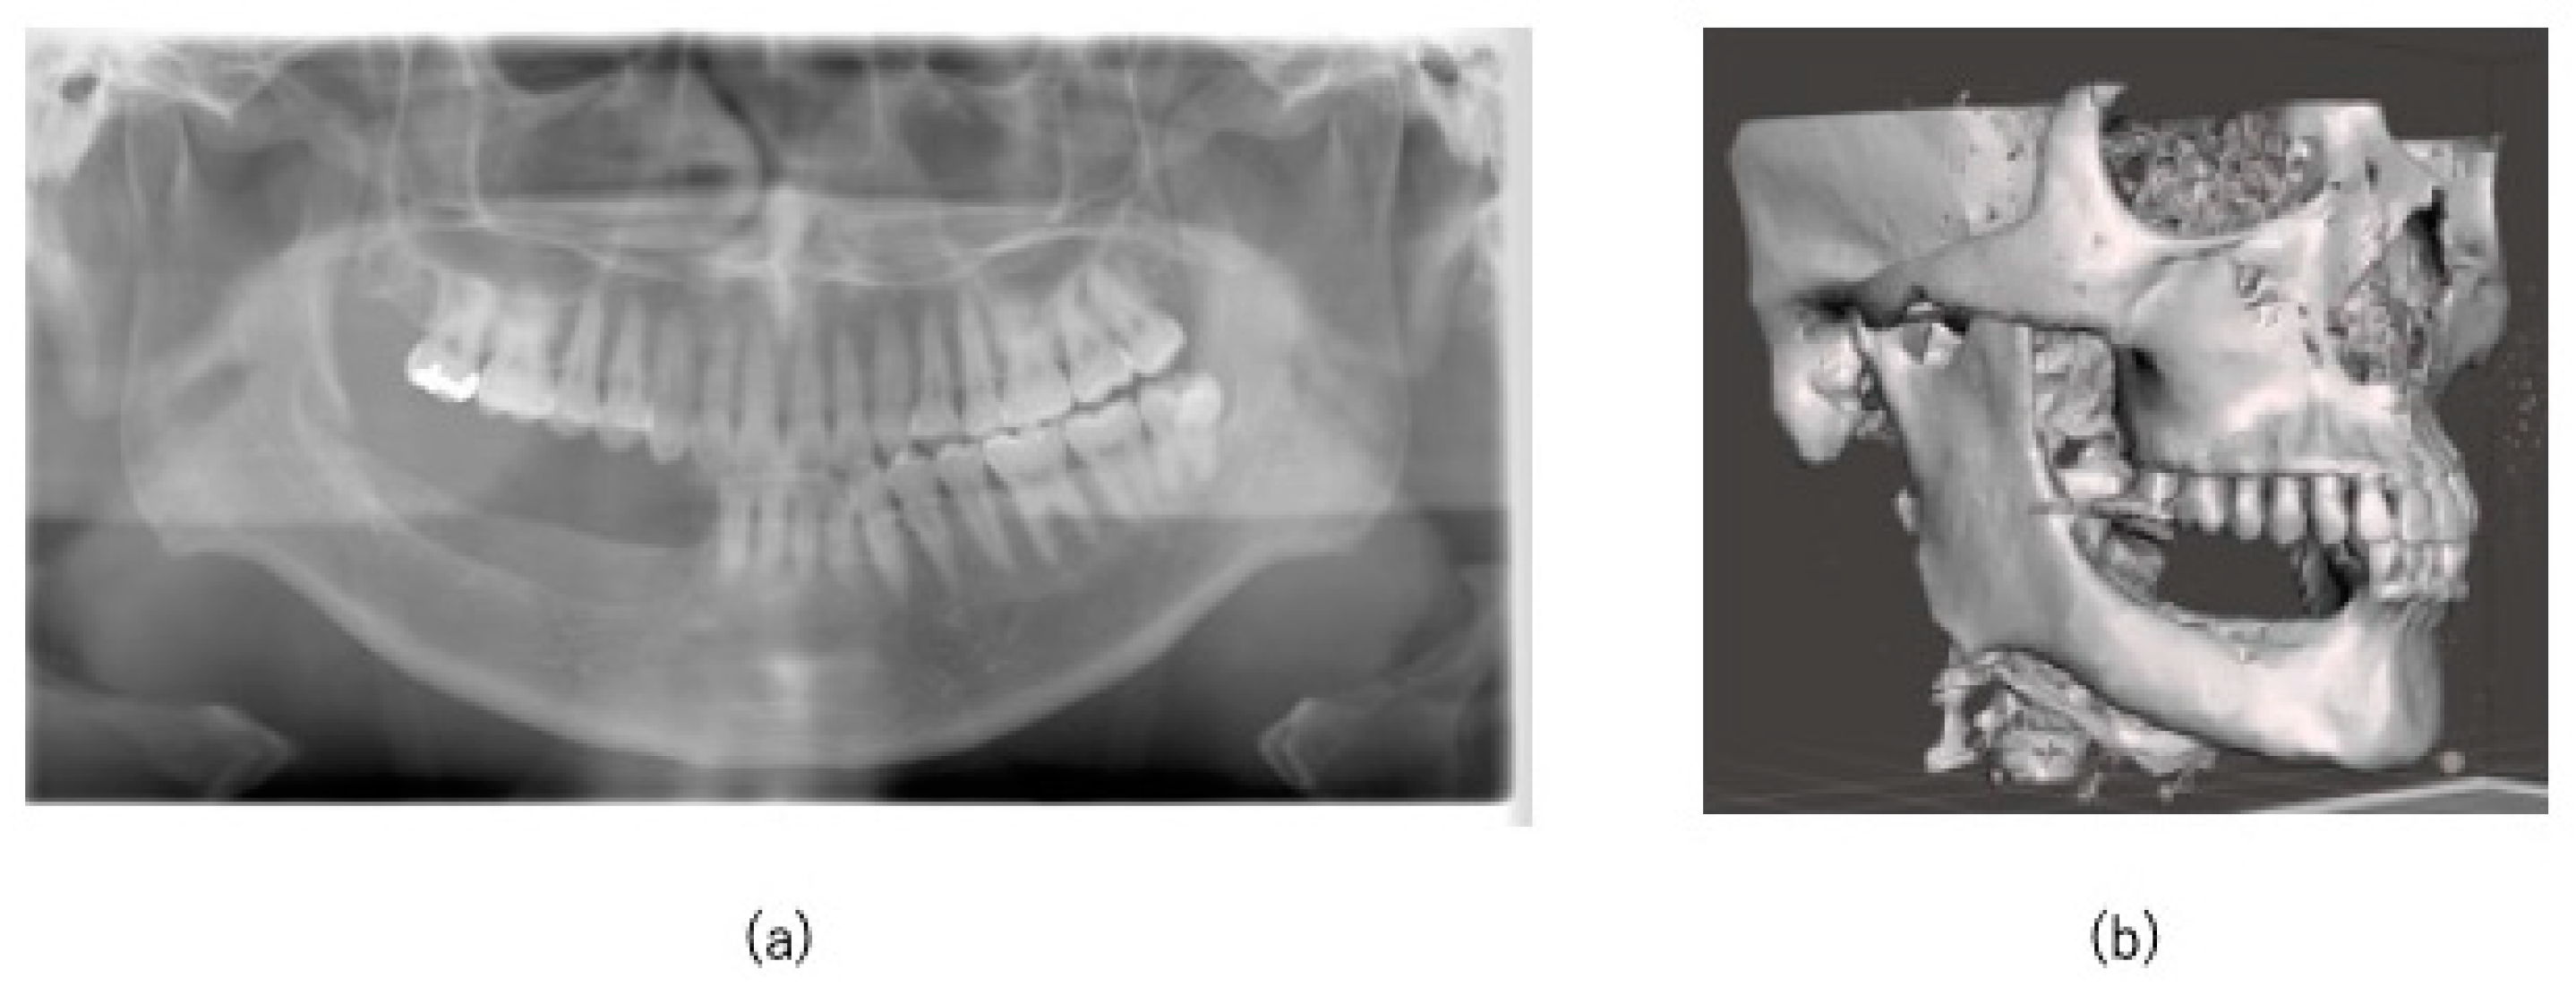

3.1. Surgical Accuracy

3.2. Postoperative Evaluation